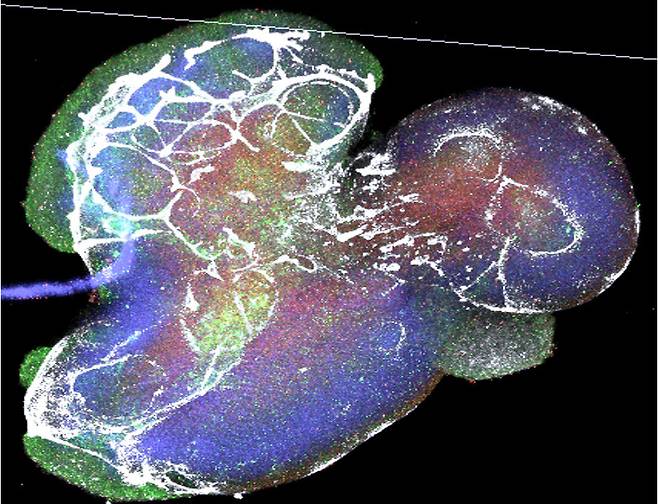

현재 기술로 우리 몸 대부분의 장기는 작은 형태로 재현되고 있다. 뇌, 척수, 눈, 귀, 혀, 침샘, 식도, 위, 대장, 소장, 항문, 간, 폐, 혈관, 심장, 콩팥, 방광, 생식기, 피부(심지어 머리털까지 달려 있다!) 등 새로운 미니장기를 만드는 데 성공했다는 논문이 나오고 있다.

이런 상피조직의 원천은 줄기세포다. 상피조직은 외부와 맞닿아 있어 늘 재생돼야 할 필요가 있는데 우리 몸속에서 상피조직을 만들어내는 능력을 가진 게 줄기세포다. 장기에서 줄기세포를 채취하거나, 아예 배아 줄기세포로부터 성체 줄기세포를 만들고 적절한 배양 조건에서 3차원으로 키우면 이 줄기세포는 미니장기가 된다. 생물학자들은 배 발생 동안 각각의 장기가 만들어지는 데 필요한 인자가 무엇인지 열심히 연구해왔고, 3차원 세포 배양 기술이 발전했으며, 줄기세포에 대한 이해가 높아지는 등의 과학적인 진보가 더해져서, 2000년대에 들어서면서 비로소 미니장기 기술이 정립됐다.

뇌를 연구하는 과학자들에게도 미니장기 기술은 특별하다. 다른 장기의 경우 환자로부터 조금 떼어내서(이걸 ‘생검’이라고 한다) 진단·연구를 하는 것이 가능하지만, 뇌는 생검이 불가능하므로 사람 뇌에 대한 인간 지식의 대부분은 죽은 이의 뇌를 대상으로 한 연구에서 나온 것이다. 그러나 미니 뇌를 이용하면 사람 뇌세포를 살아 있는 상태로 키울 수 있어, 뇌의 여러가지 특징을 들여다볼 수 있다. 사람한테서만 나타나는 뇌질환의 특징을 간파하고, 이를 정복하기 위한 연구와 약물 개발 가능성이 훨씬 높아진 것이다. 미니장기는 생물학적 기초 원리를 밝히고, 인간의 질병을 이해하고, 치료 약물을 찾거나 재생 치료를 위한 치료제로 사용 가능한 희망의 기술이다.